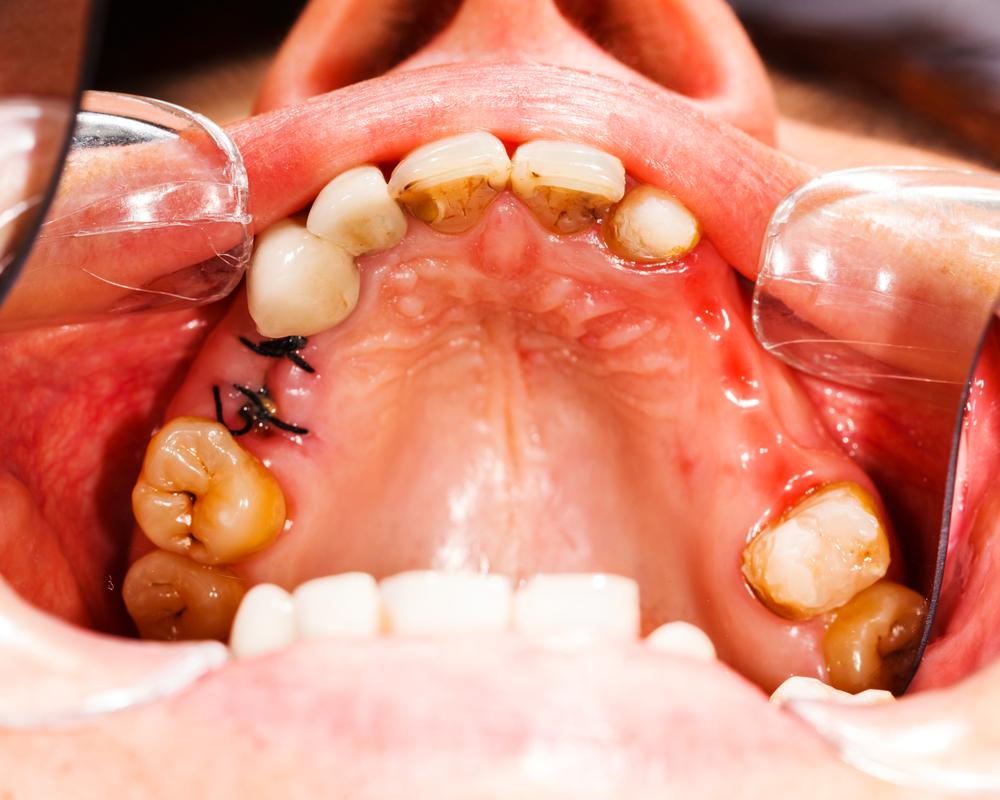

- Dark-stained pits and holes on the tooth/teeth.

- Breaking or chipping of the teeth, thus exposing a black inner surface.

There are some cavities, not visible to the naked eye that reside at the back of the mouth or between teeth. Now these cavities, although, don’t cause pain, can be identified only through ultrasound, x-rays, and/or fluorescent lighting. Therefore, it is extremely important to see your dentist regularly in order to keep your teeth in good health.